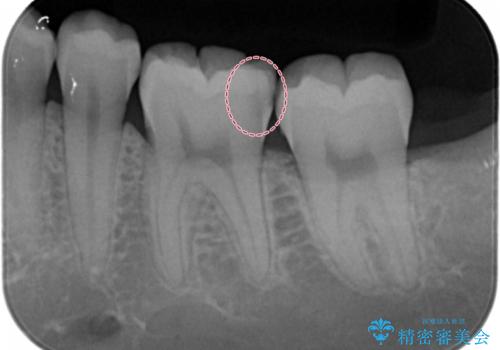

- 銀歯を白くしたいとのことで来院されました。

特に大きな虫歯もなかったため、周りの歯を残しつつセラミックインレーでの修復処置をしていきます。

大きな虫歯さえなければ、銀歯のやり替えは詰め物の周りの歯を保存しつつ修復することができます。